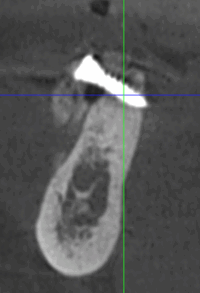

Lorsque l’os de la mâchoire est insuffisant pour soutenir un implant dentaire, des techniques de reconstruction osseuse peuvent être nécessaires. Ces procédures permettent d’augmenter le volume osseux pour garantir la stabilité de l’implant.

- Greffe osseuse : Ajout d’os ou de matériaux pour augmenter le volume osseux.

- Régénération Osseuse Guidée : Stimule la repousse osseuse grâce à des biomatériaux.

- Sinus Lift : Augmentation de l’os dans la région des molaires supérieures par élévation des sinus.